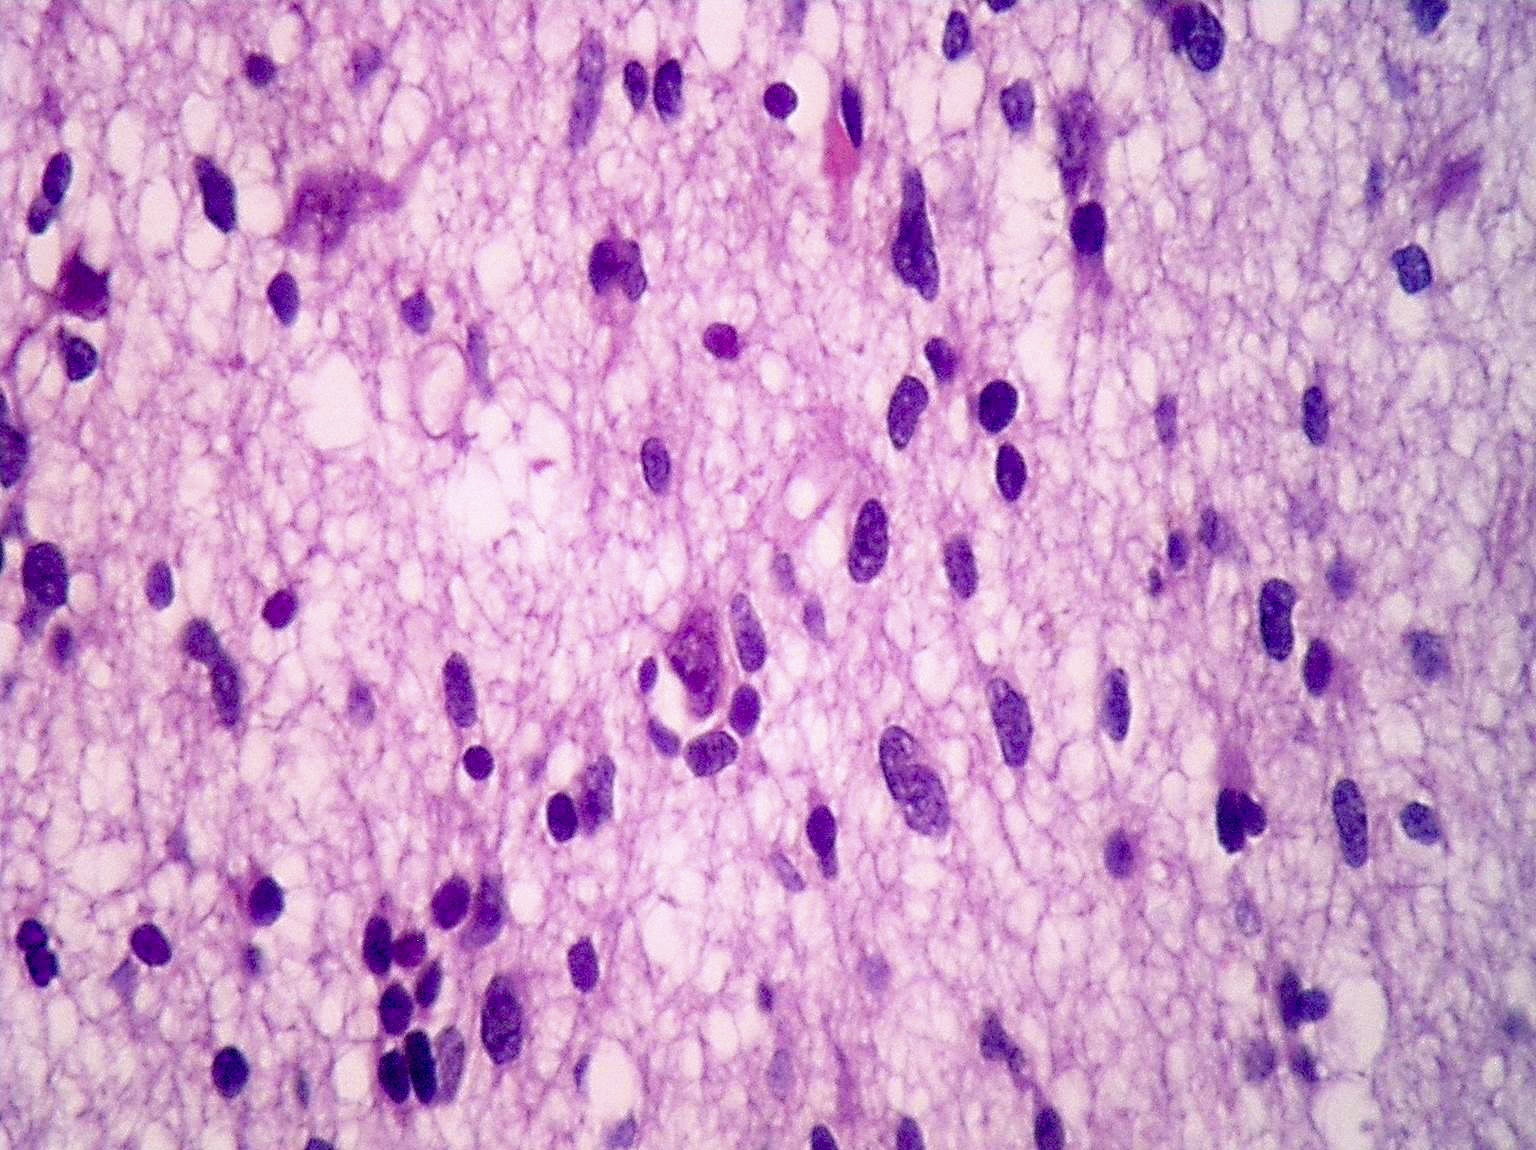

Microscopic (histologic) description

- Diffusely infiltrating tumor cells with oval to elongated astrocytic nuclei and varying appearance of tumor cytoplasm and fibrillar glial processes (Acta Neuropathol 2015;129:789)

- At the periphery, tumor cells may infiltrate in a diffuse single cell pattern, often with entrapped neurons and axons

- Cellular morphology is variable, even within a single tumor

- Commonly there is a mix of cells with elongated nuclei and fine fibrillar processes, cells with eccentric nuclei and glassy eosinophilic cytoplasm (gemistocytes), larger pleomorphic cells and small cells with scant cytoplasm

- May show oligodendroglioma-like areas

- Myxoid background and microcyst formation may be present

- Variable mitotic activity, cellularity and nuclear atypia depending on CNS WHO grade

- In small biopsy specimens, the presence of 1 mitosis may be sufficient for a CNS WHO grade 3 diagnosis, while the presence of a few mitotic figures in a large resection would not be sufficient for grade 3 designation (Acta Neuropathol 2020;139:603)

- Presence of necrosis or microvascular proliferation would be consistent with a CNS WHO grade 4 designation

Microscopic (histologic) images

Contributed by Eman Abdelzaher, M.D., Ph.D., John DeWitt, M.D., Ph.D. and Meaghan Morris, M.D., Ph.D.